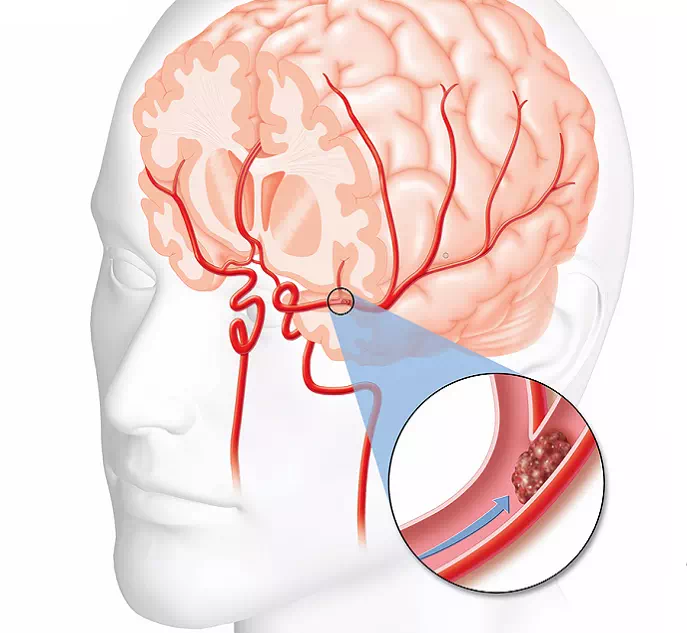

Инсульт — это состояние, которое возникает в результате нарушения кровоснабжения мозга, что может привести к различным физическим и когнитивным осложнениям. Реабилитация после инсульта играет важную роль в восстановлении потерянных навыков и функций.